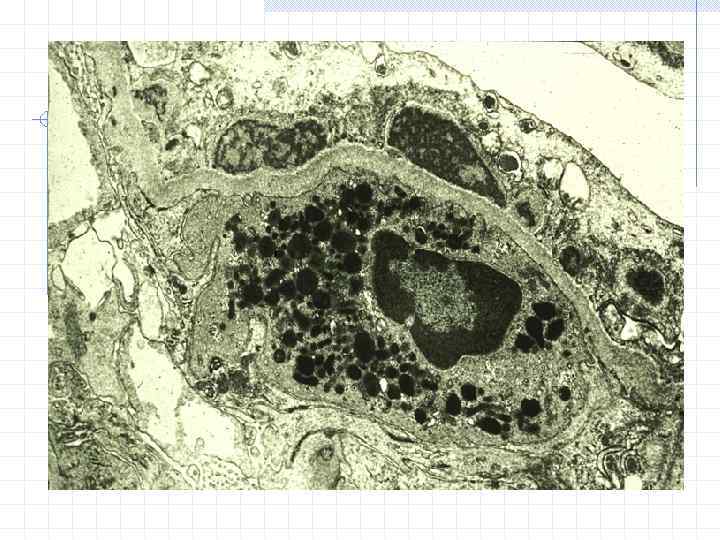

Нейтрофил Диффузный генерализованный эксудативно-пролиферативный гломерулонефрит, субэпителиальные депозиты ( «горбы» )